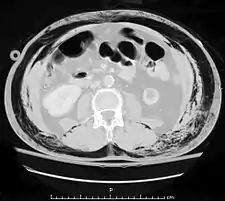

El intestino delgado ocupa gran parte del abdomen y puede resultar dañado en lesiones penetrantes.[3] El intestino puede resultar perforado, y la presencia de gas en la cavidad abdominal visualizada en una tomografía axial computarizada se interpreta como un signo diagnóstico de perforación intestinal.[4] Sin embargo, la presencia de aire en la cavidad intra-abdominal también puede ser por causa de neumotórax—aire en la cavidad pleural fuera de los pulmones que se ha escapado de las vías respiratorias—o neumomediastino—aire en el mediastino, el centro de la cavidad torácica—.[4] Una lesión intestinal puede estar asociada con complicaciones tales como infección, absceso, obstrucción intestinal, y la formación de fístulas. La perforación intestinal debe ser reparada quirúrgicamente.[4]

Un estudio encontró que el diez por ciento de pacientes politraumatizados que no tenían signos clínicos de lesión abdominal tenían evidencias radiológicas de imagen de tales lesiones.[1] Las técnicas de diagnóstico más utilizadas incluyen la tomografía, ecografía, y rayos X.[5] Los rayos X pueden ayudar a determinar el trayecto de un objeto penetrante y localizar cualquier objeto extraño que queda en la herida, pero no suele ser útil en el traumatismo contuso.[5]

La ecografía puede detectar fluidos como la sangre o contenido gastrointestinal en la cavidad abdominal y es un procedimiento no invasivo y relativamente seguro para el paciente.[4] La tomografía computarizada de exploración es la técnica preferida para las personas que no están en riesgo inmediato de choque,[13] pero ya que la ecografía se puede realizar en una sala de emergencia, este último se recomienda para personas que no están lo suficientemente estables como para pasar al tomógrafo.[1] Sin embargo, los pacientes con traumatismo abdominal con frecuencia necesitan la tomografía computarizada para otros traumatismos concomitantes, por ejemplo, cráneo o tórax. En estos casos, la TAC abdominal se puede realizar al mismo tiempo, sin perder tiempo en la atención de los pacientes.[4]